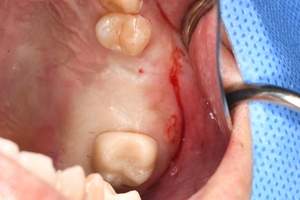

症例写真-1

- Befor

- After

症例写真-2

- 途中経過

| 年齢 | 50代・男性 |

| 主訴 | 右下歯が疼く |

| 治療内容 | ・右下6番インプラント ※1:FGG(遊離歯肉移植術)とは、足りない歯ぐきを上顎から上皮を切り取り移植する外科手術 |

| 治療費 | 合計:902,000円(税込) ■内訳 |

| 治療期間 | 9ヵ月 |

| 治療方針 | 右下の当該歯は歯根破折により保存不可能と診断しました。歯周疾患も伴っていたため抜歯後に骨吸収※1が大きく起こることが予測できました。チタンメッシュ併用骨再生誘導法(GBR※2)を選択しインプラント埋入と同時に行い自然な歯槽骨のラインを再現しました。またGBRを行う際にインプラント辺縁の付着歯肉の減少が起こる為、遊離歯肉移植術(FGG※3)を行い清掃性を考慮した形態に仕上げました。 ■治療方針の解説 治療した右下の歯をレントゲンで撮影したところ根本の部分に黒く写る箇所があり「根尖性慢性周囲炎※1」と診断。また歯周病も進行していました。 ※1 骨吸収・・・歯槽骨という歯を支える骨がなくなっていくこと |

| 担当者所見 | 主訴の右下だけでなく歯茎の腫れ、発赤があり不良補綴や不良充填など他にも治療箇所が多数ありました。プラークコントロールが不良であった為まずはブラッシング指導を行いセルフケアの重要性を理解していただくところからスタートしました。 右下6番の歯はインプラント治療を行なった結果審美的にも機能的にも患者様の満足を得ることができました。骨造成と歯肉移植も行なった為インプラントを支える十分な歯周組織の獲得ができたと思っております。 |